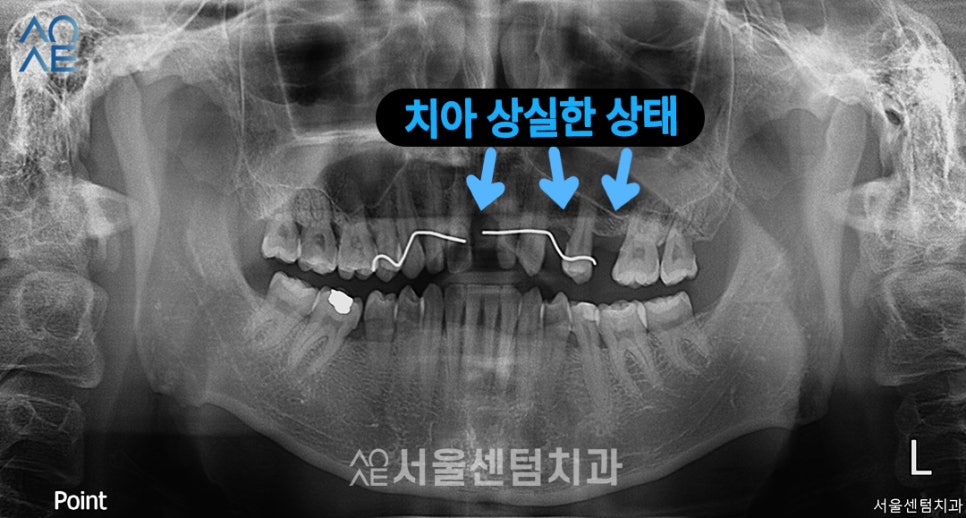

이 분의 경우엔 치아가 이미 상실한 상태라

본인도 임플란트가 필요하다는 점을

인지한 상태로 내원해주셨습니다.

앞니와 어금니를 상실하셨고

잇몸도 전체적으로 많이 내려와있는 상태였죠.

복합적인 치료가 필요하기에

엑스레이 사진과 함께 차근차근 설명해드렸습니다.

(엑스레이에선 왼/오가 반대로 나옵니다)

| (1) 현재 상태🔹 앞니1개, 어금니 3개 상실🔹 전체적으로 잇몸 많이 내려가 있는 상태🔹오른쪽 위에는 식립할 공간 부족 |